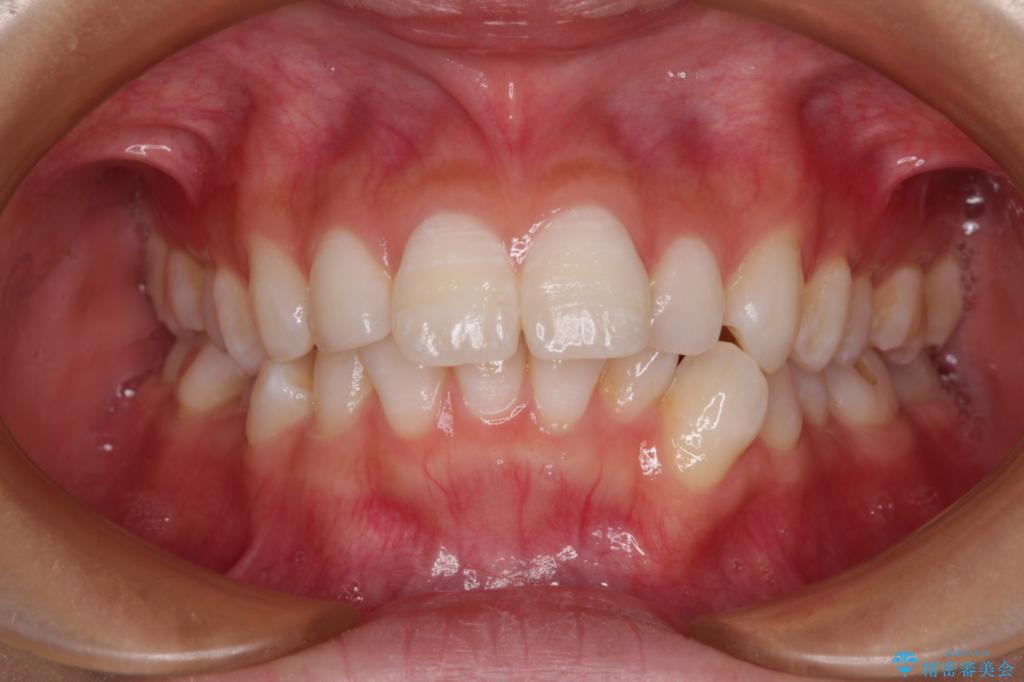

下唇に前歯が当たって跡が残ってしまう状態でしたが、スッキリとした口元に仕上げることができました。

下顎はデコボコが気になっていたため、上下左右第一小臼歯4本を抜去して、ワイヤー装置にて口元の突出感を改善するよう矯正治療を行うこととしました。